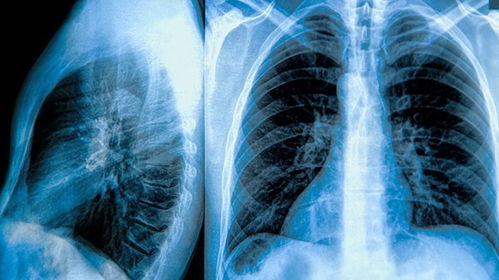

03 做好康复方案。当你去医院看医生时,他会给你做一些病理检查,以确定你是否真的患有肺炎。确诊后,医生会建议你吃药或打针来进行治疗,病情严重的话,需要住院治疗。当你看医生时,他会先对你进行简单的身体检查,然后再进行一些其它的病理测试。医生会用听诊器听诊你的呼吸音,看你呼吸的时候有没有哮鸣音、水泡音和低沉而持续的声音,对于听不到呼吸音的肺部区域,医生会让你做一个胸部X射线检查。注意:目前尚无针对病毒性肺炎的治疗方法。此类肺炎不能使用抗生素治疗,但医生会给你开抗病毒药物,并告诉你该做什么。对于重度肺炎,你需要进行住院治疗,期间会接受抗生素治疗、输液治疗,甚至是输氧来治疗肺炎。